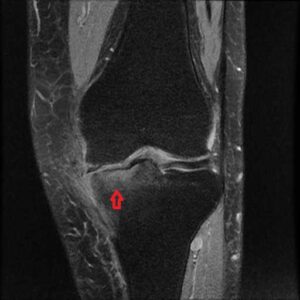

膝関節MRIでみられる骨髄浮腫 (bone marrow edema:BME)は、痛みの強さを表します。